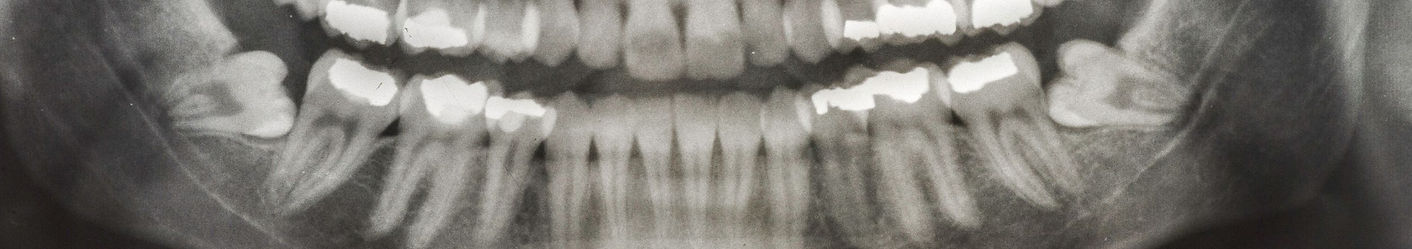

Digital X-rays help assess nerve proximity, allowing the dentist to plan the safest surgical approach.

X-rays assess nerve proximity, essential for safe planning of surgical extraction.